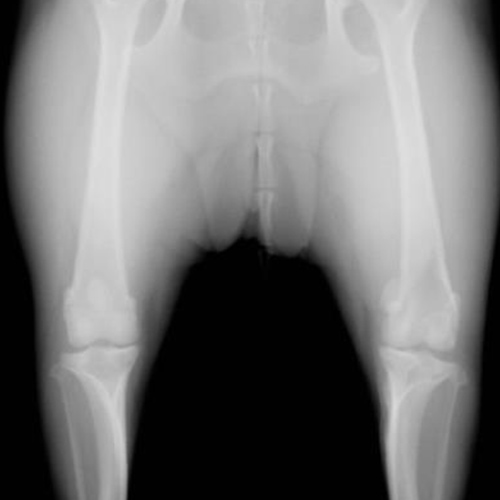

膝蓋骨内方脱臼のX線写真です。(2枚とも同じ症例)

黄色い丸で示された膝蓋骨が反対側と比較して内側にずれているのが確認できます。この脱臼により、膝本来の正常な曲げ伸ばしが障害され、時間をかけて様々な問題を併発させます。